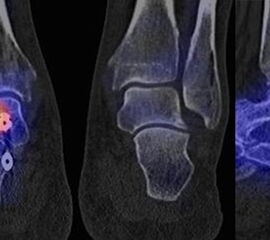

Abbildung 2.2.

Bilder eines Patienten mit Z. n. mehrfachen Sprunggelenksdistorsionen in der Vergangenheit, besonders heftige Distorsion des linken Sprunggelenkes 5 Wochen vor der Untersuchung. Die SPECT/CT zeigt eine instabile osteochondrale Läsion mit deutlicher Aktivierung.

Zum Lesen der Bildbeschreibung und zur Vollansicht bitte das Bild anklicken. Bild: H. C. Rischke